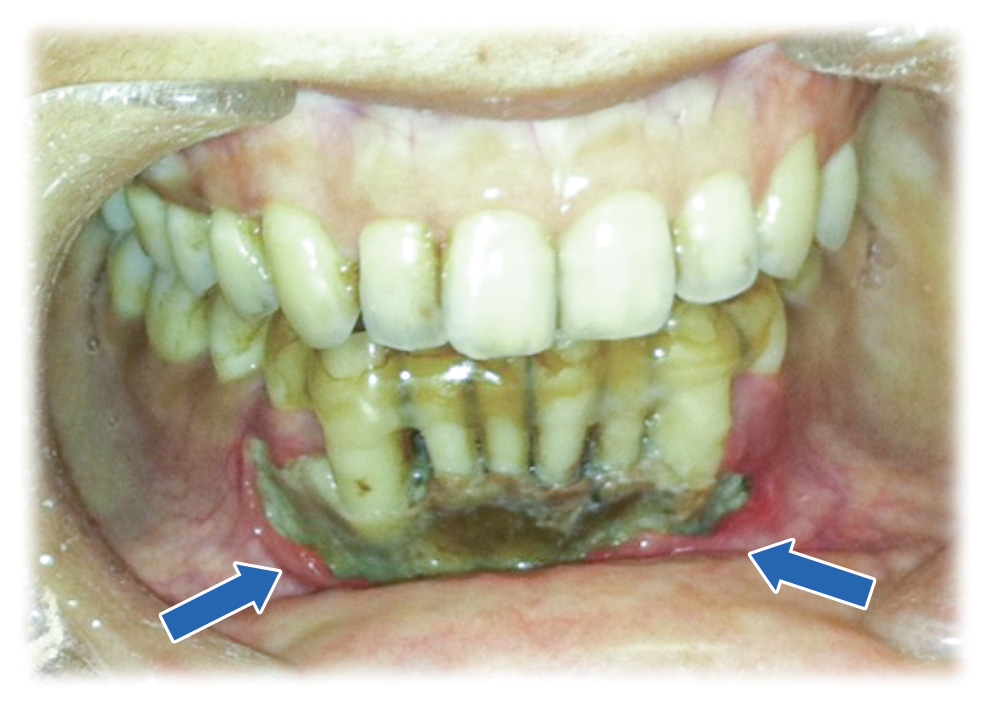

壊死した下顎骨が歯茎から露出しています(矢印の範囲)。

壊死骨の中の歯はグラグラになっているため固定しています。